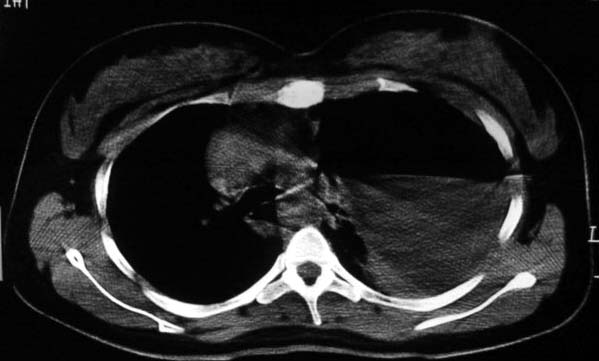

标题: CT5517:女性、24岁,反复胸痛、气促不能平卧半月。 [打印本页]

标题: CT5517:女性、24岁,反复胸痛、气促不能平卧半月。

左侧气液腔与胃腔影相连,考虑膈疝。钡餐检查有助于诊断。

我看这是膈疝,在纵隔窗第六\\七幅图像上可见胃粘膜影,再者可见两个腔影,这在液气胸是不会有的.

支持膈疝,纵隔窗内可见消化道的内容物。

“反复胸痛、气促不能平卧半月”。+影像学表现=膈疝